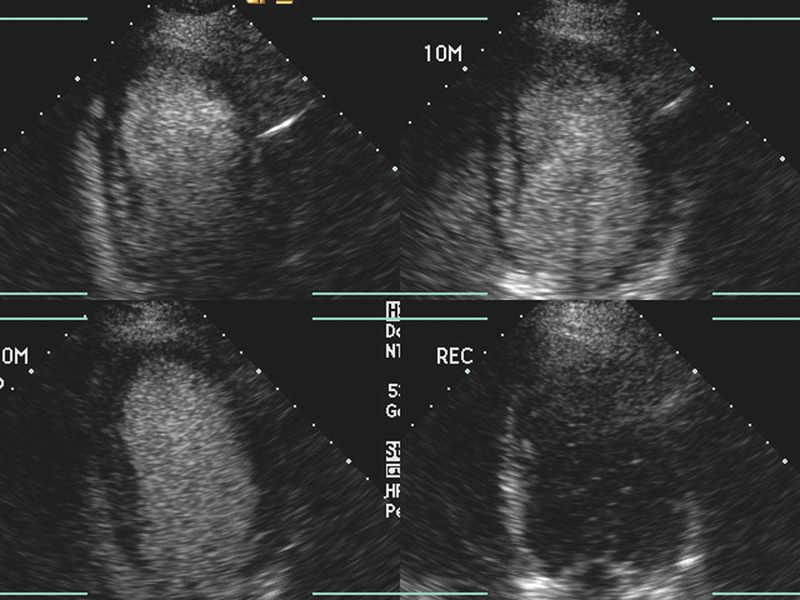

فحوصات تشخيصية لبعض امراض القلب والشرايين التاجية